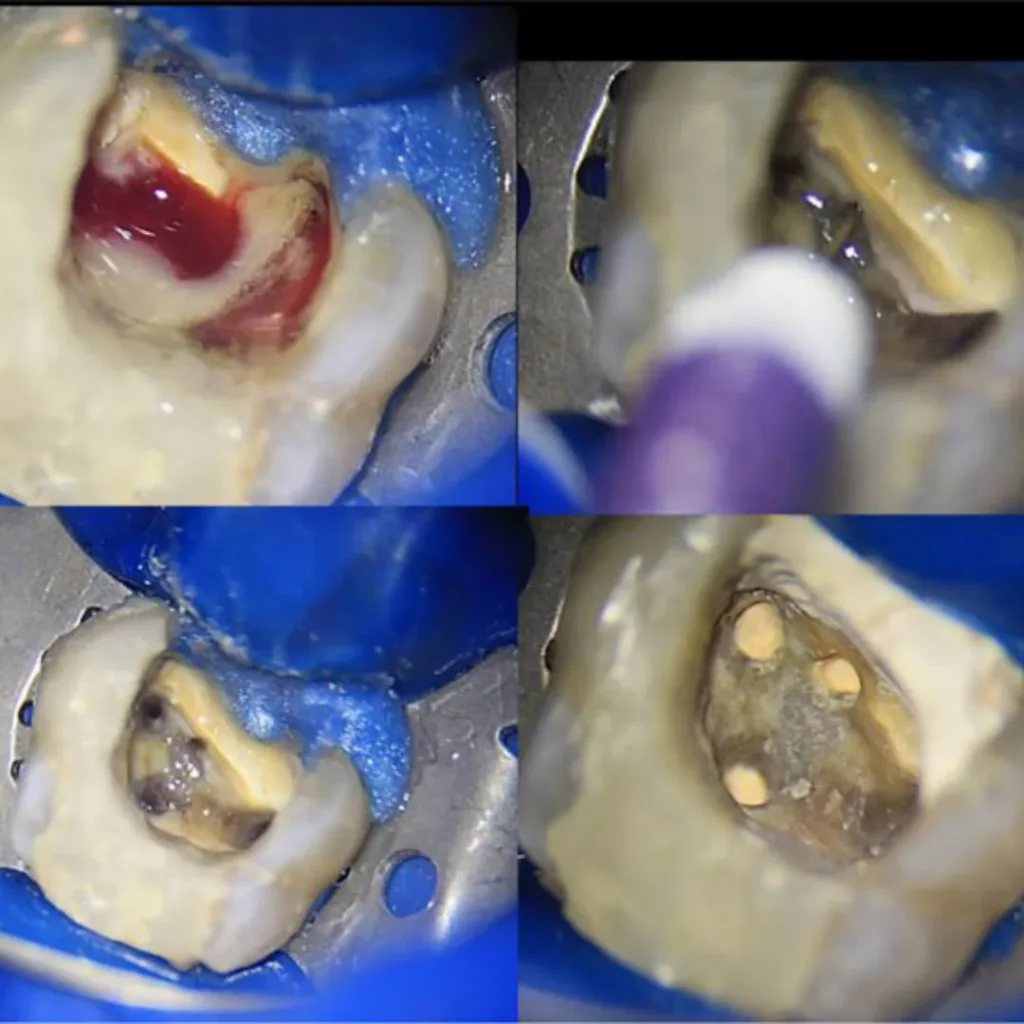

درمان ریشه یا اندودانتیکس یکی از حساسترین و تخصصیترین خدمات دندانپزشکی است که در کلینیک نیکا توسط متخصصین مجرب و با استفاده از تجهیزات دیجیتال پیشرفته انجام میشود. این درمان زمانی انجام میشود که پالپ دندان (بافت نرم داخل ریشه) دچار التهاب یا عفونت شده باشد. در کلینیک نیکا، مراحل درمان شامل تصویربرداری دقیق با دستگاههای دیجیتال، بیحسی موضعی بدون درد، پاکسازی کامل کانالهای ریشه و پرکردن آنها با مواد زیستسازگار است. استفاده از لوپهای بزرگنمایی و فایلهای روتاری باعث افزایش دقت و کاهش احتمال شکست درمان میشود

در این فرآیند، دندانپزشک با استفاده از ابزارهای تخصصی، پالپ آلوده را خارج کرده Pulpectomy، کانالهای ریشه را پاکسازی و ضدعفونی میکند Canal Disinfection، سپس آنها را با مواد پرکننده مخصوص مانند گوتاپرکا (Gutta-Percha) مهر و موم مینماید. در بسیاری موارد، برای افزایش دوام و عملکرد، از روکش دندان Dental Crown استفاده میشود.